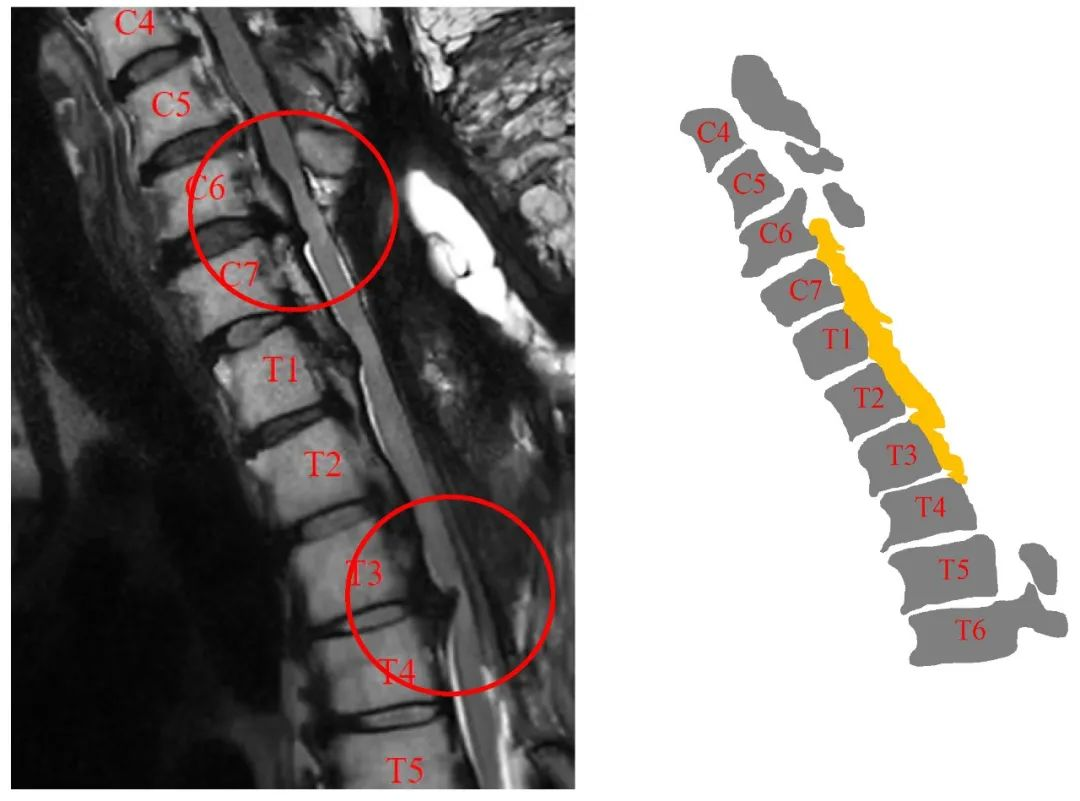

病史:M, 34 y/o

Numbness of right lower limb for 2 months, weakness for 1 week

Urination disorder

Body Weight: 120Kg; BMI: 39.5

影像资料:

Thoracic spinal stenosis(T2-T3)

Thoracic spinal stenosis decompression(T2-T3)